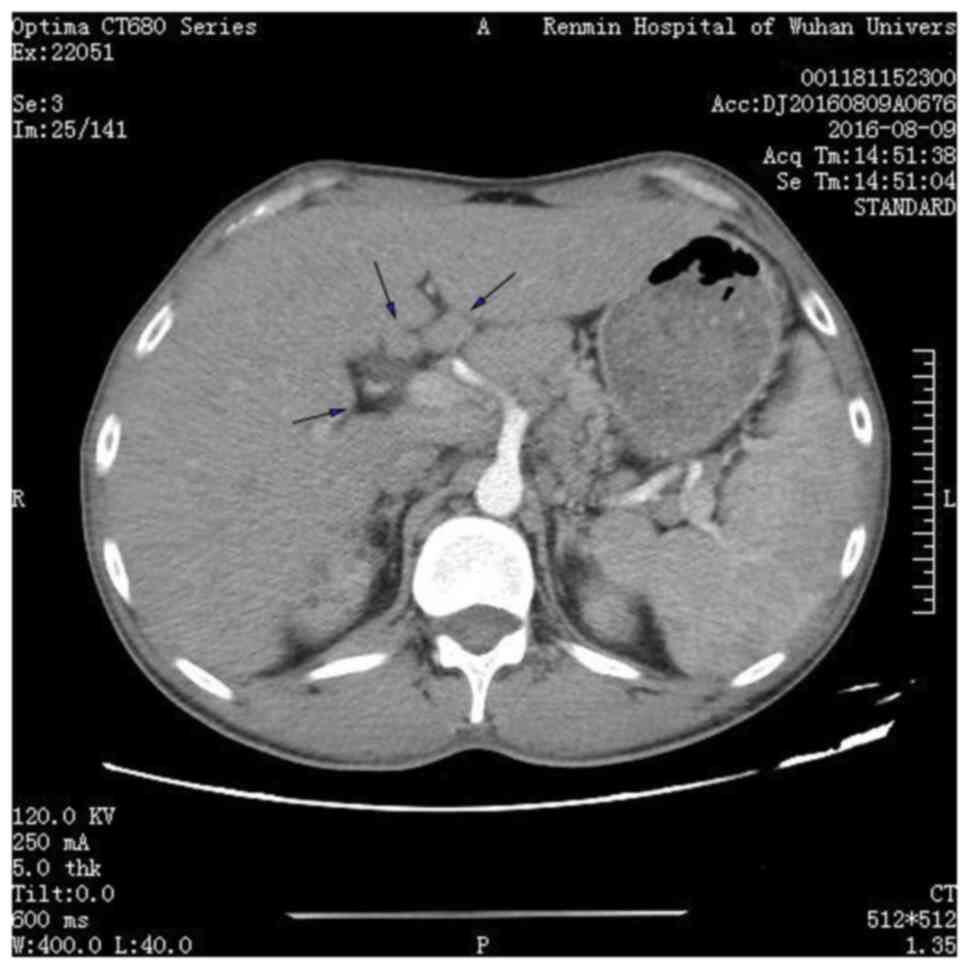

Deep lymph node enlargement and renal failure caused by hypercalcemia‑associated sarcoidosis: A case report

Sarcoidosis is a rare disease that severely affects the lungs and superficial lymph nodes. In addition, this disease can also affect the skin, eyes and kidneys to varying degrees. The present report described a 32‑year‑old male patient who was admitted to Renmin Hospital of Wuhan University (Wuhan, China) due to joint pain in the extremities. He was diagnosed with uncorrectable hypercalcemia. A lymph node biopsy revealed the hypercalcemia to be associated with sarcoidosis, with the patient also demonstrating renal failure and lymph node enlargement. Administration of glucocorticoids provided benefits in terms of both primary and recurrent sarcoidosis, which also improved and preserved renal function. After being prescribed with oral prednisone treatment, blood calcium levels returned to normal, which indicated markedly improving renal function. However, the discontinuation of glucocorticoids for 2 months resulted in increased serum calcium and creatinine levels, both of which returned to abnormal levels. Overall, the present case report suggests that clinicians should actively perform sarcoidosis treatment in clinical practice to overcome any unexpected results associated with organ damage.

Figure 3

Figure 4